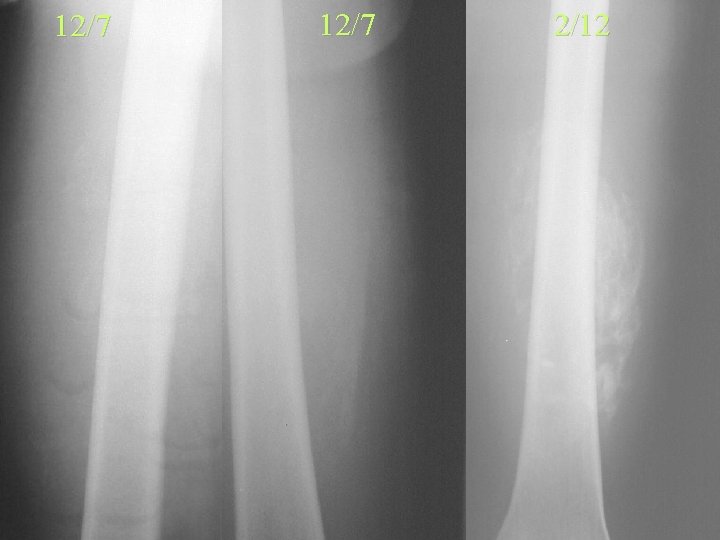

12/7 2/12

Myositis Ossificans • 4/52 Faint peripheral Ca – Periosteal reaction • 8/52 Circumscribed cortex – Central lacy pattern • 5/12 Maturity • >6/12 Regression – Separate from bone • 1 year Usually disappears – Periosteal reaction remains

Post Traumatic Myositis Ossificans Centrifugal Ossification Neoplastic Soft Tissue Ossification Centripetal Ossification